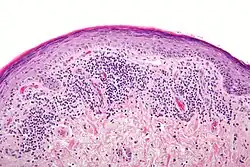

Histopathology of lichen planus

The histologic findings of oral LP can offer strong support for the diagnosis, but are not pathognomonic. Clinical correlation is required. Common histologic findings of oral LP include:[47]

• Parakeratosis and slight acanthosis of the epithelium

• Saw-toothed rete ridges

• Liquefaction (hydropic) degeneration of the basal layer with apoptotic keratinocytes (referred to as Civatte, colloid, hyaline, or cytoid bodies)

• An amorphous band of eosinophilic material at the basement membrane composed of fibrin or fibrinogen.

• A lichenoid (band-like) lymphocytic infiltrate immediately subjacent to the epithelium.

Nonetheless, interpreting the histopathological features of oral LP has been associated historically with high intra-observer and inter-observer variabilities.[66]